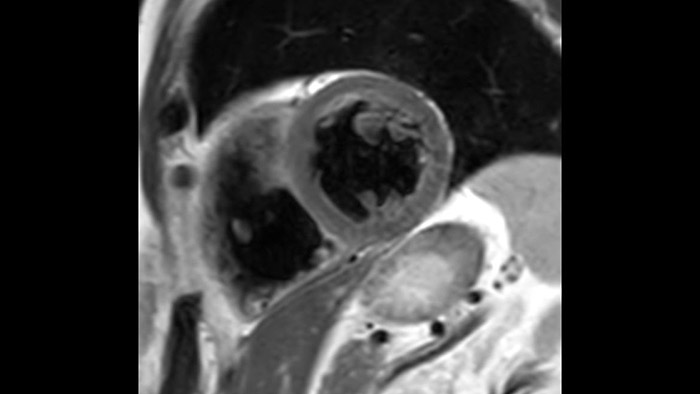

A utilidade do diagnóstico e prognóstico da RM cardíaca está a aumentar. Avalie a anatomia e função do coração utilizando aquisições cine, adquira informações sobre a perfusão e viabilidade do tecido cardíaco, visualize potenciais edemas com sequência de sangue escuro, aceda e quantifique mesmo a caracterização do tecido com a CardiacQuant.

Os diagnósticos tradicionais não têm a visibilidade necessária para ver os efeitos do tratamento cardíaco ou para detetar disfunção antes que os sintomas ocorram. Ao combinar a sequência de aquisição de RM da Philips Fast-SENC com a ferramenta de análise MyoStrain da Myocardial Solutions, as alterações precoces e subtis da função cardíaca podem ser medidas diretamente.